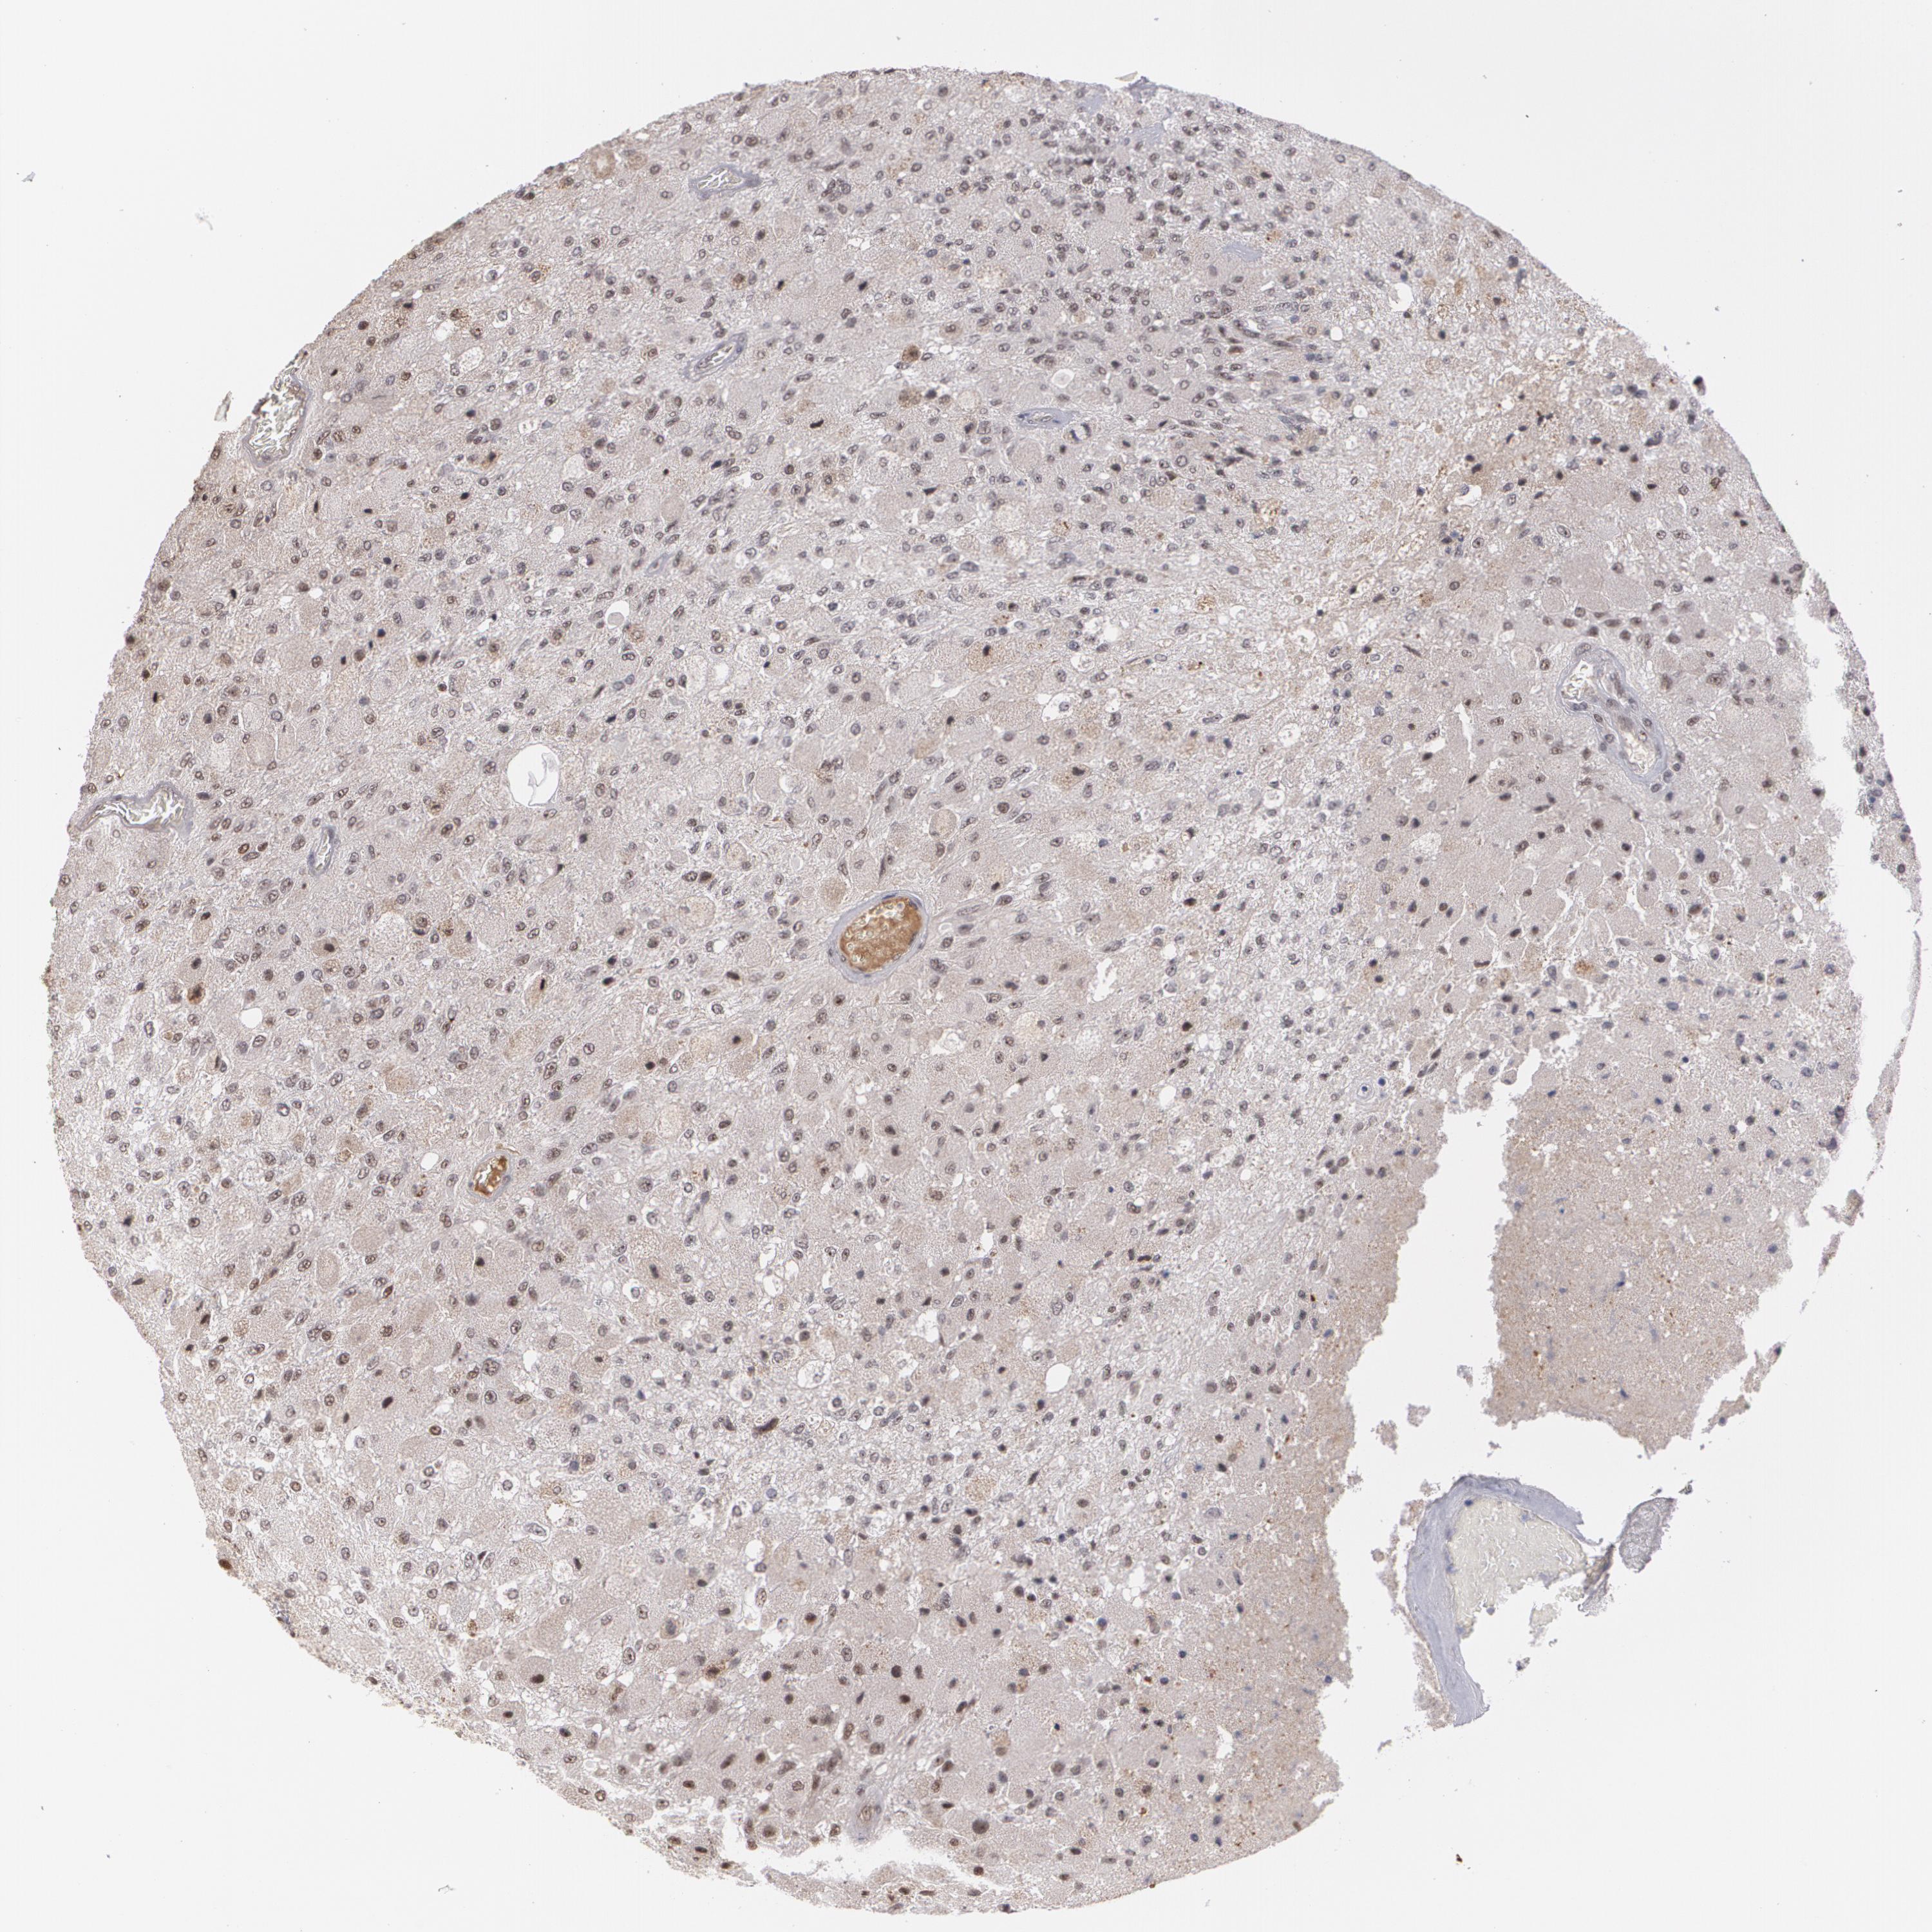

GLIOMA - Protein expressioni

A mouse-over function shows sample information and annotation data. Click on an image to view it in a full screen mode. Samples can be filtered based on level of antibody staining by selecting one or several of the following categories: high, medium, low and not detected. The assay and annotation is described here.

Note that samples used for immunohistochemistry by the Human Protein Atlas do not correspond to samples in the TCGA dataset.

Antibody stainingi

Antibody staining in the annotated cell types in the current human tissue is reported as not detected, low, medium, or high, based on conventional immunohistochemistry profiling in selected tissues. This score is based on the combination of the staining intensity and fraction of stained cells.

Each image is clickable and will lead to virtual microscopy that enables deeper exploration of all samples and also displays staining intensity scores, fraction scores and subcellular localization as well as patient and tissue information for each sample.

Antibody HPA001664

Staining

High

Medium

Low

Not detected

Intensity

Strong

Moderate

Weak

Negative

Quantity

>75%

75%-25%

<25%

None

Location

Nuclear

Cytoplasmic/membranous

Cytoplasmic/membranous,nuclear

Glioma, malignant, High grade

Glioma, malignant, NOS

Glioma, malignant, Low grade